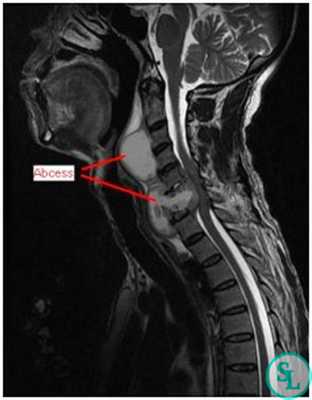

В диагностике заболеваний позвоночника большей популярностью пользуется магнитно-резонансная томография (или точнее «ядерно-магнитно-резонансная»), более безопасная и чувствительная, чем жесткое рентгеновское излучение. На снимках костные структуры получаются черными, но мягкие ткани, наполненные водой, передают все оттенки серого и белого цветов. Это позволяет обнаруживать мельчайшие объекты (узелковые образования, инфильтрации) и отслеживать динамику развития абсцесса.

- МРТ позвоночника. Определяется снижение интенсивности сигнала на Т1-взвешенных снимках и его повышение на Т2-взвешенных изображениях, деформация межпозвоночных дисков, структурные изменения тел позвонков. Чувствительность магнитно-резонансной томографии достигает 96%, точность - 94%, поэтому ее считают «золотым стандартом» диагностики.

Абсцесс в межпозвоночном пространстве создает эмбол (пузырек) с истонченными стенками, внутри которого повышенное давление жидкого содержимого вызывает болезненные ощущения в позвоночнике: корешки спинномозговых нервов сигнализируют о раздражении, создаваемом выпирающими краями фиброзного кольца.